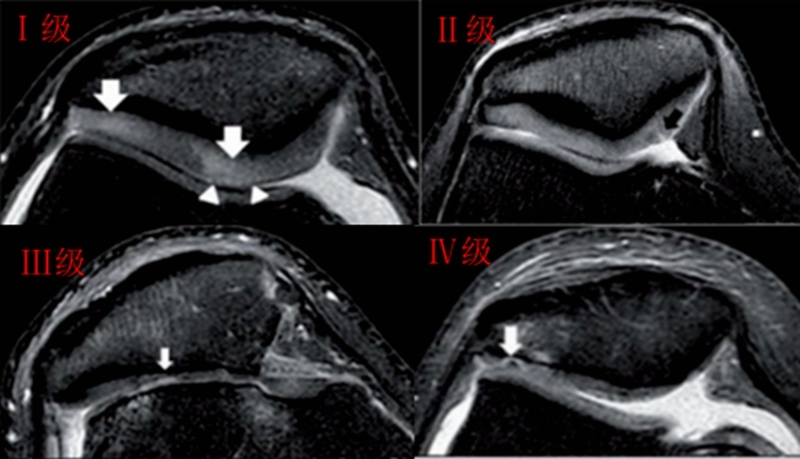

髌骨软骨软化分级表现

Ⅰ级:关节软骨失去珍珠样外观而变得较暗淡,局部软化,肿胀区或纤毛化区的直径<0.5cm。

Ⅱ级:关节软骨软化区内出现毛刷状或纤毛化改变,深达1-2mm,直径≤1.3cm。

Ⅲ级:软骨的毛刷状或纤毛化改变达关节软骨厚度一半以上,直径>1.3cm,关节软骨表面类似蟹肉样改变,表面有多发软骨碎片附着其下的软骨。

Ⅳ级:关节软骨全层受侵,软骨下骨暴露,表现为进展期髌股关节炎。

Ⅰ~Ⅱ级为早期,主要保守治疗,Ⅲ~Ⅳ级为进展期,需要手术及关节镜治疗。